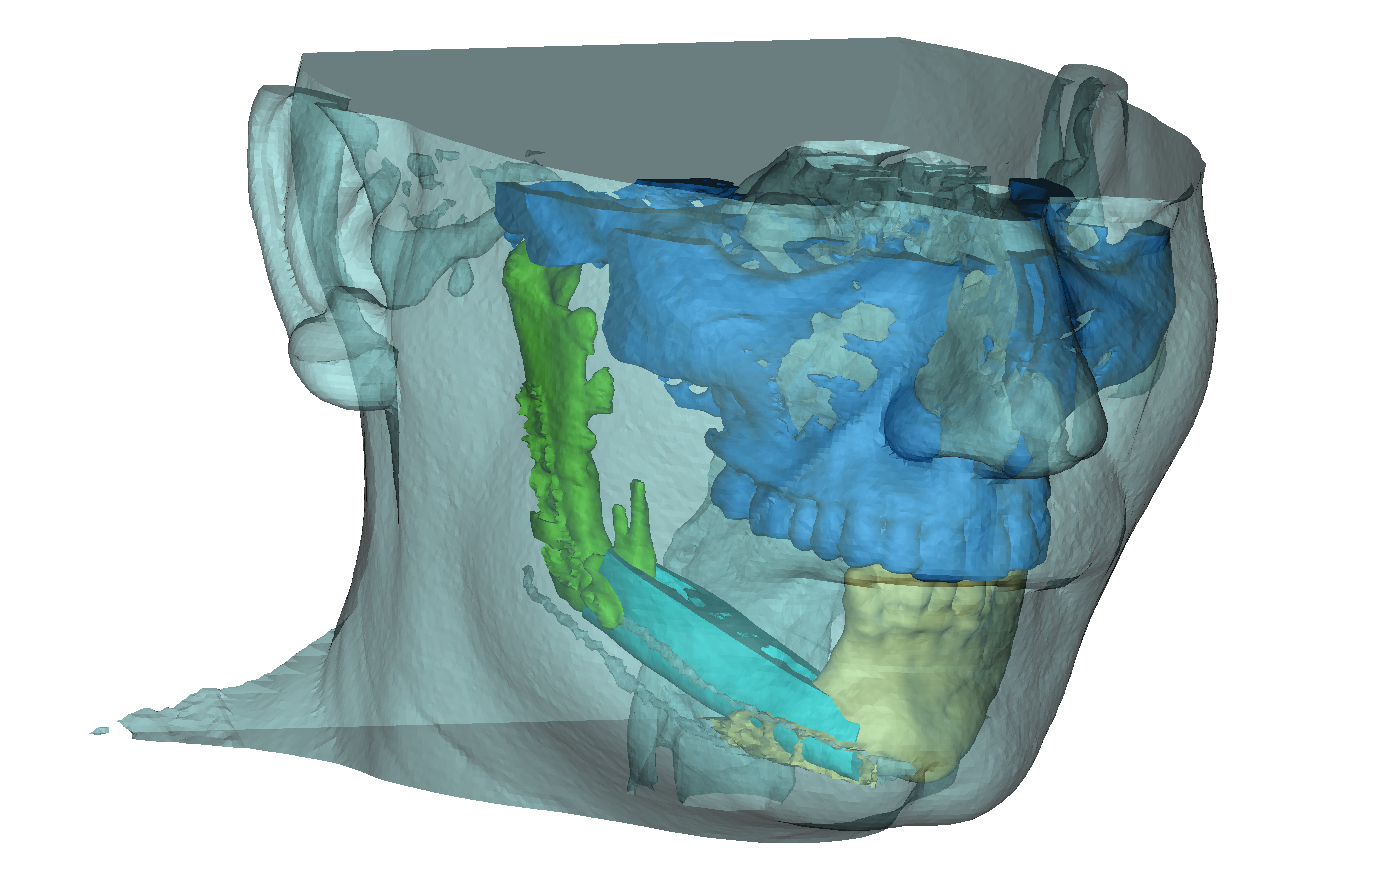

Εξατομικευμένη Χειρουργική Κεφαλής, Τραχήλου και Μαστού με χρήση Τρισδιάστατης Ιατρικής Εκτύπωσης

Σήμερα για πρώτη φορά στην Ελλάδα, το Metropolitan Hospital ενσωματώνει την Τρισδιάστατη Ιατρική Εκτύπωση (Medical 3D Printing) στην καθημερινή ιατρική πράξη και πιο συγκεκριμένα στην Αισθητική και Επανορθωτική Χειρουργική Κεφαλής, Τραχήλου και Μαστού.

Το γεγονός αυτό σημαίνει ότι μια χειρουργική επέμβαση μπορεί να σχεδιαστεί και...